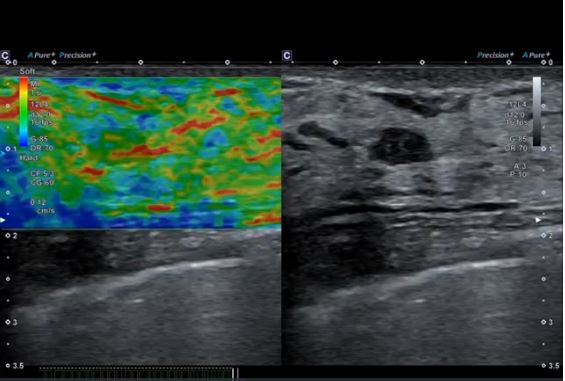

Нова вдосконалена технологія компресійної елестографії Strain Elastography забезпечує покращену часову та просторову роздільну здатність, високу відтворюваність і дозволяє вибирати ROI навіть після замороження кадру.

Однорідність структури щитовидної залози демонструється за допомогою лінійного датчика PLU-805BT.